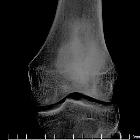

CT

- central intramedullary hypodense cystic lesion with thick rim ossification

- extensive thick well-circumscribed periosteal reaction and bone sclerosis around the lesion could be seen